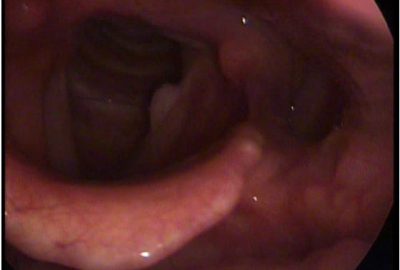

Αμυγδαλεκτομή

Η αμυγδαλεκτομή είναι μια από τις συχνότερες επεμβάσεις που πραγματοποιούνται στην παιδική ηλικία.

Οι ενδείξεις της αμυγδαλεκτομής, όπως και για όλα τα χειρουργεία, χωρίζονται στις απόλυτες και τις σχετικές.

Οι απόλυτες ενδείξεις για την αμυγδαλεκτομή στην παιδική ηλικία είναι κυρίως το ροχαλητό με αποφρακτική υπνική άπνοια (δηλαδή διακοπή της αναπνοής του παιδιού κατά την διάρκεια του ύπνου του). Επίσης δυο επεισόδια αποστημάτων των αμυγδαλών καθώς και πιο σπάνιες παθήσεις.

Οι σχετικές ενδείξεις είναι τα πολλαπλά επεισόδια μικροβιακών αμυγδαλιτίδων, ένα επεισόδιο αποστήματος των αμυγδαλών κακοσμία στόματος οφειλόμενο στις αμυγδαλές, κλπ

Η ηλικία που πραγματοποιούνται οι επεμβάσεις αυτές είναι συνήθως μετά τα τρία (3) έτη του παιδιού. Βεβαία είναι δυνατό να χειρουργηθεί και παιδί μικρότερης ηλικίας αν η κατάστασή του εμπνέει ανησυχία. Στα παιδιά αυτά προσπαθούμε να διατηρήσουμε ένα μέρος της αμυγδαλής (αμυγδαλοτομή).